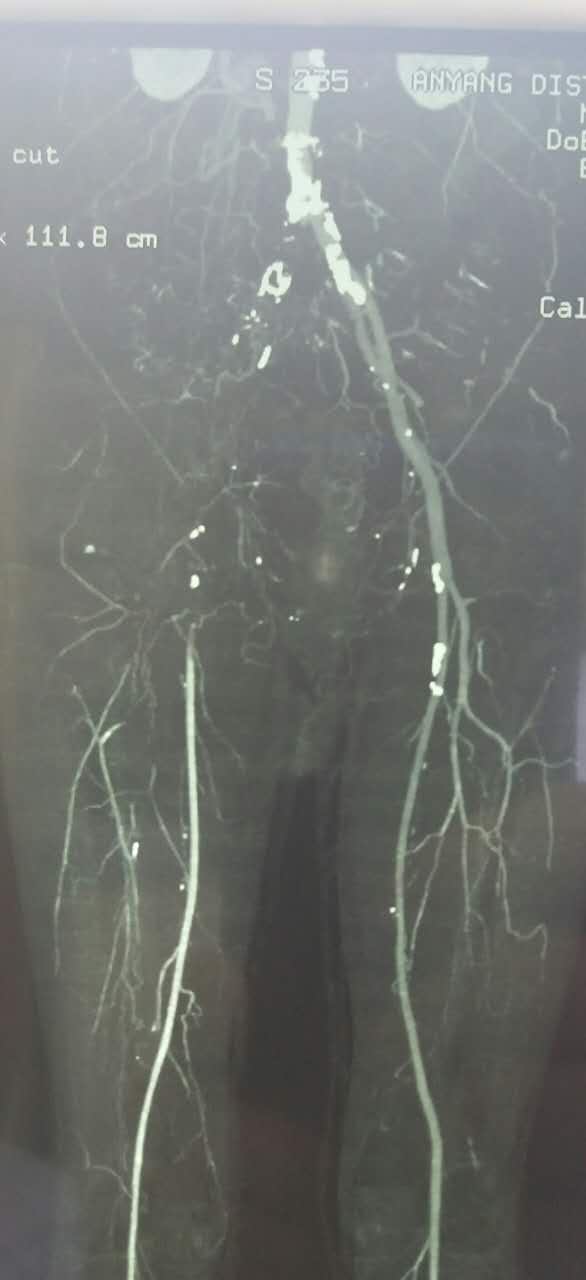

术前经讨论,考虑股深动脉的重要性,决定开刀取栓基础上对残余狭窄介入治疗。

患者平卧位,常规消毒铺单,局麻下切开显露右侧股总动脉和股深动脉、股浅动脉。全身肝素化后,切开股动脉,对股浅动脉取栓后远侧回血好,对股深动脉反复取栓后出现汹涌回血。近端取栓后用导丝导管通过闭塞段到达腹主动脉下段,造影证实在真腔,用5*80mm球囊扩张后造影,髂动脉内有部分充盈缺损。植入巴德Fluency8*100和8*60覆膜支架后用7*60球囊扩张,造影管腔光滑(如图)。缝合动脉切口,关闭伤口,术毕。

术后右侧胫后动脉可以触及清晰搏动。